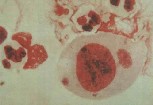

一、急性淋病:原发性尿道炎、潜伏期:急性淋病的潜伏期很短,通常在性接触后2~5天,很少数患者潜伏期可长达10天。淋菌侵入男性尿道后要经历三个阶段, ①侵入阶段:淋菌侵入后需36小时才能深入该处粘膜浅层,并开始繁殖生长。 ②发育阶段:约36小时内完成一个生活周期。 ③排毒阶段:生活周期后,部分淋菌死亡,排出内毒素类物质,从而引起机体组织对毒素的反应,此时才出现临床症状。

2、尿道口红肿溢脓 经12~24小时后疼痛略微减轻,并开始排出稀薄的粘液样分泌物,量多,再经12~24小时,排出大量的脓性分泌物,24小时可排出脓汁20~50ml。2~3天后脓汁量减少,稠浓,颜色由白色变为黄白色或黄褐色,再经3~4天脓汁更少而浓稠,晨间由于脓液在尿道口聚集,形成脓膜,称为“糊口”,疼痛减轻,尿道口红肿,呈外翻状,包皮内叶也红肿,并可发展为包皮炎,嵌顿包茎等。

6、查体:尿道口及入状窝红肿充血、水肿,有时有小的、浅表性脓肿、糜烂或小溃疡。严重时尿道粘膜外翻,红肿波及整个头,及包皮外翻,包皮无法上翻,压迫尿道可流出脓汁。两侧腹股沟淋巴结亦可受累引起红肿、痉痛、化脓,有明显压痛,并随着尿道炎症的减轻而减少,炎症消失后2~3天,淋巴结的炎症也随之消失。